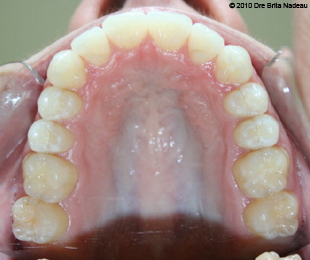

Marie-Hélène Cyr - Upper occlusal view - After orthodontic treatments and orthognathic surgeries (January 29, 2010)

January 29, 2010 - This upper occlusal view of my teeth is very impressive.